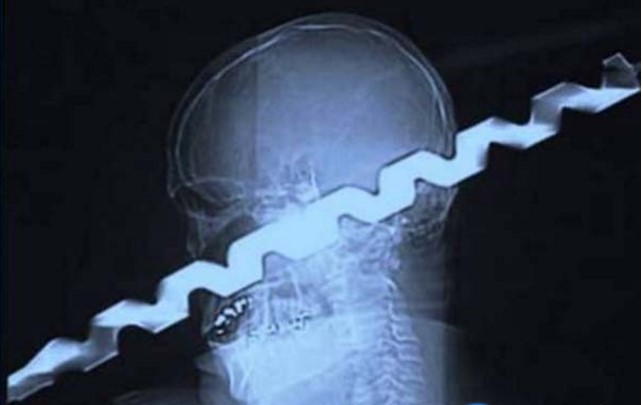

8. Gunting.